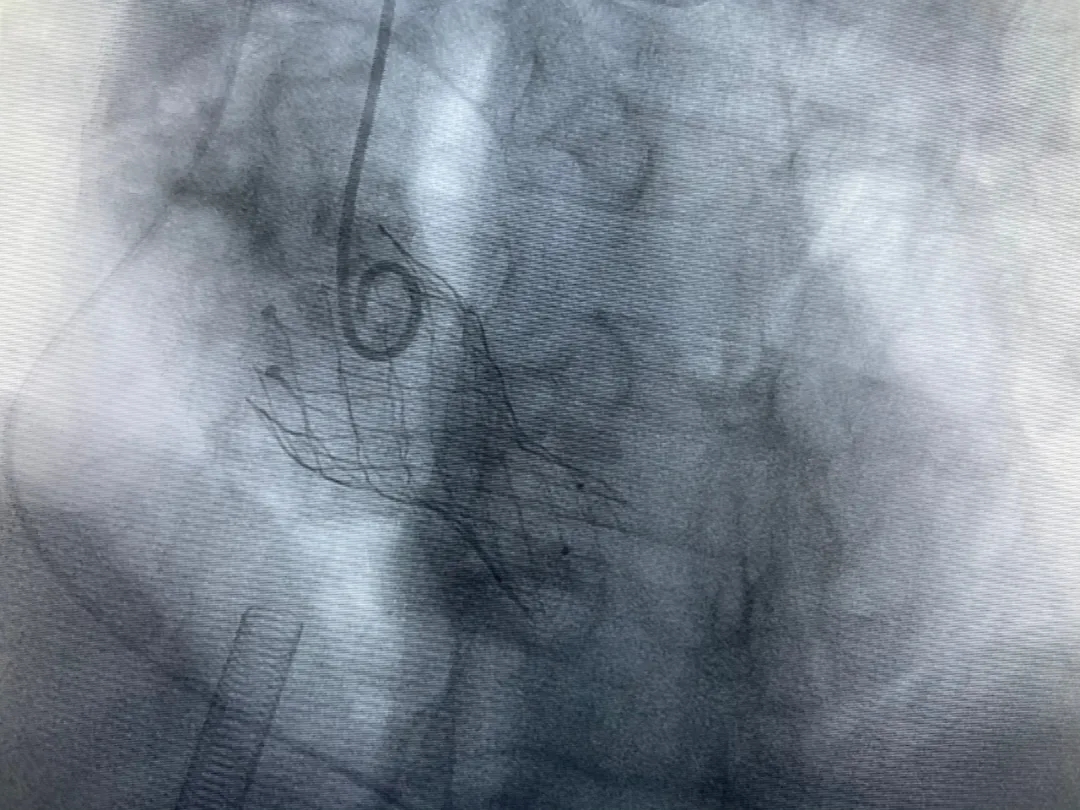

結(jié)合老人病情特點(diǎn):年齡高、室壁厚、左室腔小、瓣膜鈣化嚴(yán)重,術(shù)中球囊擴(kuò)張和瓣膜釋放過程有循環(huán)崩潰可能;為降低此種風(fēng)險(xiǎn)、最大程度提高手術(shù)成功率,張金洲副院長在術(shù)前組織了由楊金保博士帶領(lǐng)的TAVR團(tuán)隊(duì)多次反復(fù)溝通、討論,制定了各種應(yīng)急處理方案。最終經(jīng)過TAVR團(tuán)隊(duì)的默契配合,手術(shù)歷時(shí)2小時(shí),用20#球囊預(yù)擴(kuò)張后順利植入23#主動(dòng)脈瓣生物瓣膜,再次后擴(kuò)后主動(dòng)脈根部造影顯示:人工主動(dòng)脈瓣生物瓣位置良好,瓣葉開閉正常;冠脈顯影良好。經(jīng)食道超聲顯示:主動(dòng)脈瓣葉活動(dòng)度良好,主動(dòng)脈跨瓣壓差約35mmHg,未見瓣周漏及明顯返流。出手術(shù)室前老人便已蘇醒,自訴憋悶癥狀完全消失。